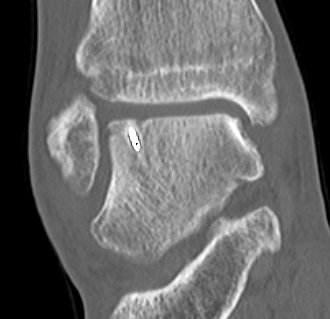

CT

Stage III

Stage IV displaced fragment with osteochondral defect

CT assessment of bony healing post ORIF with screws